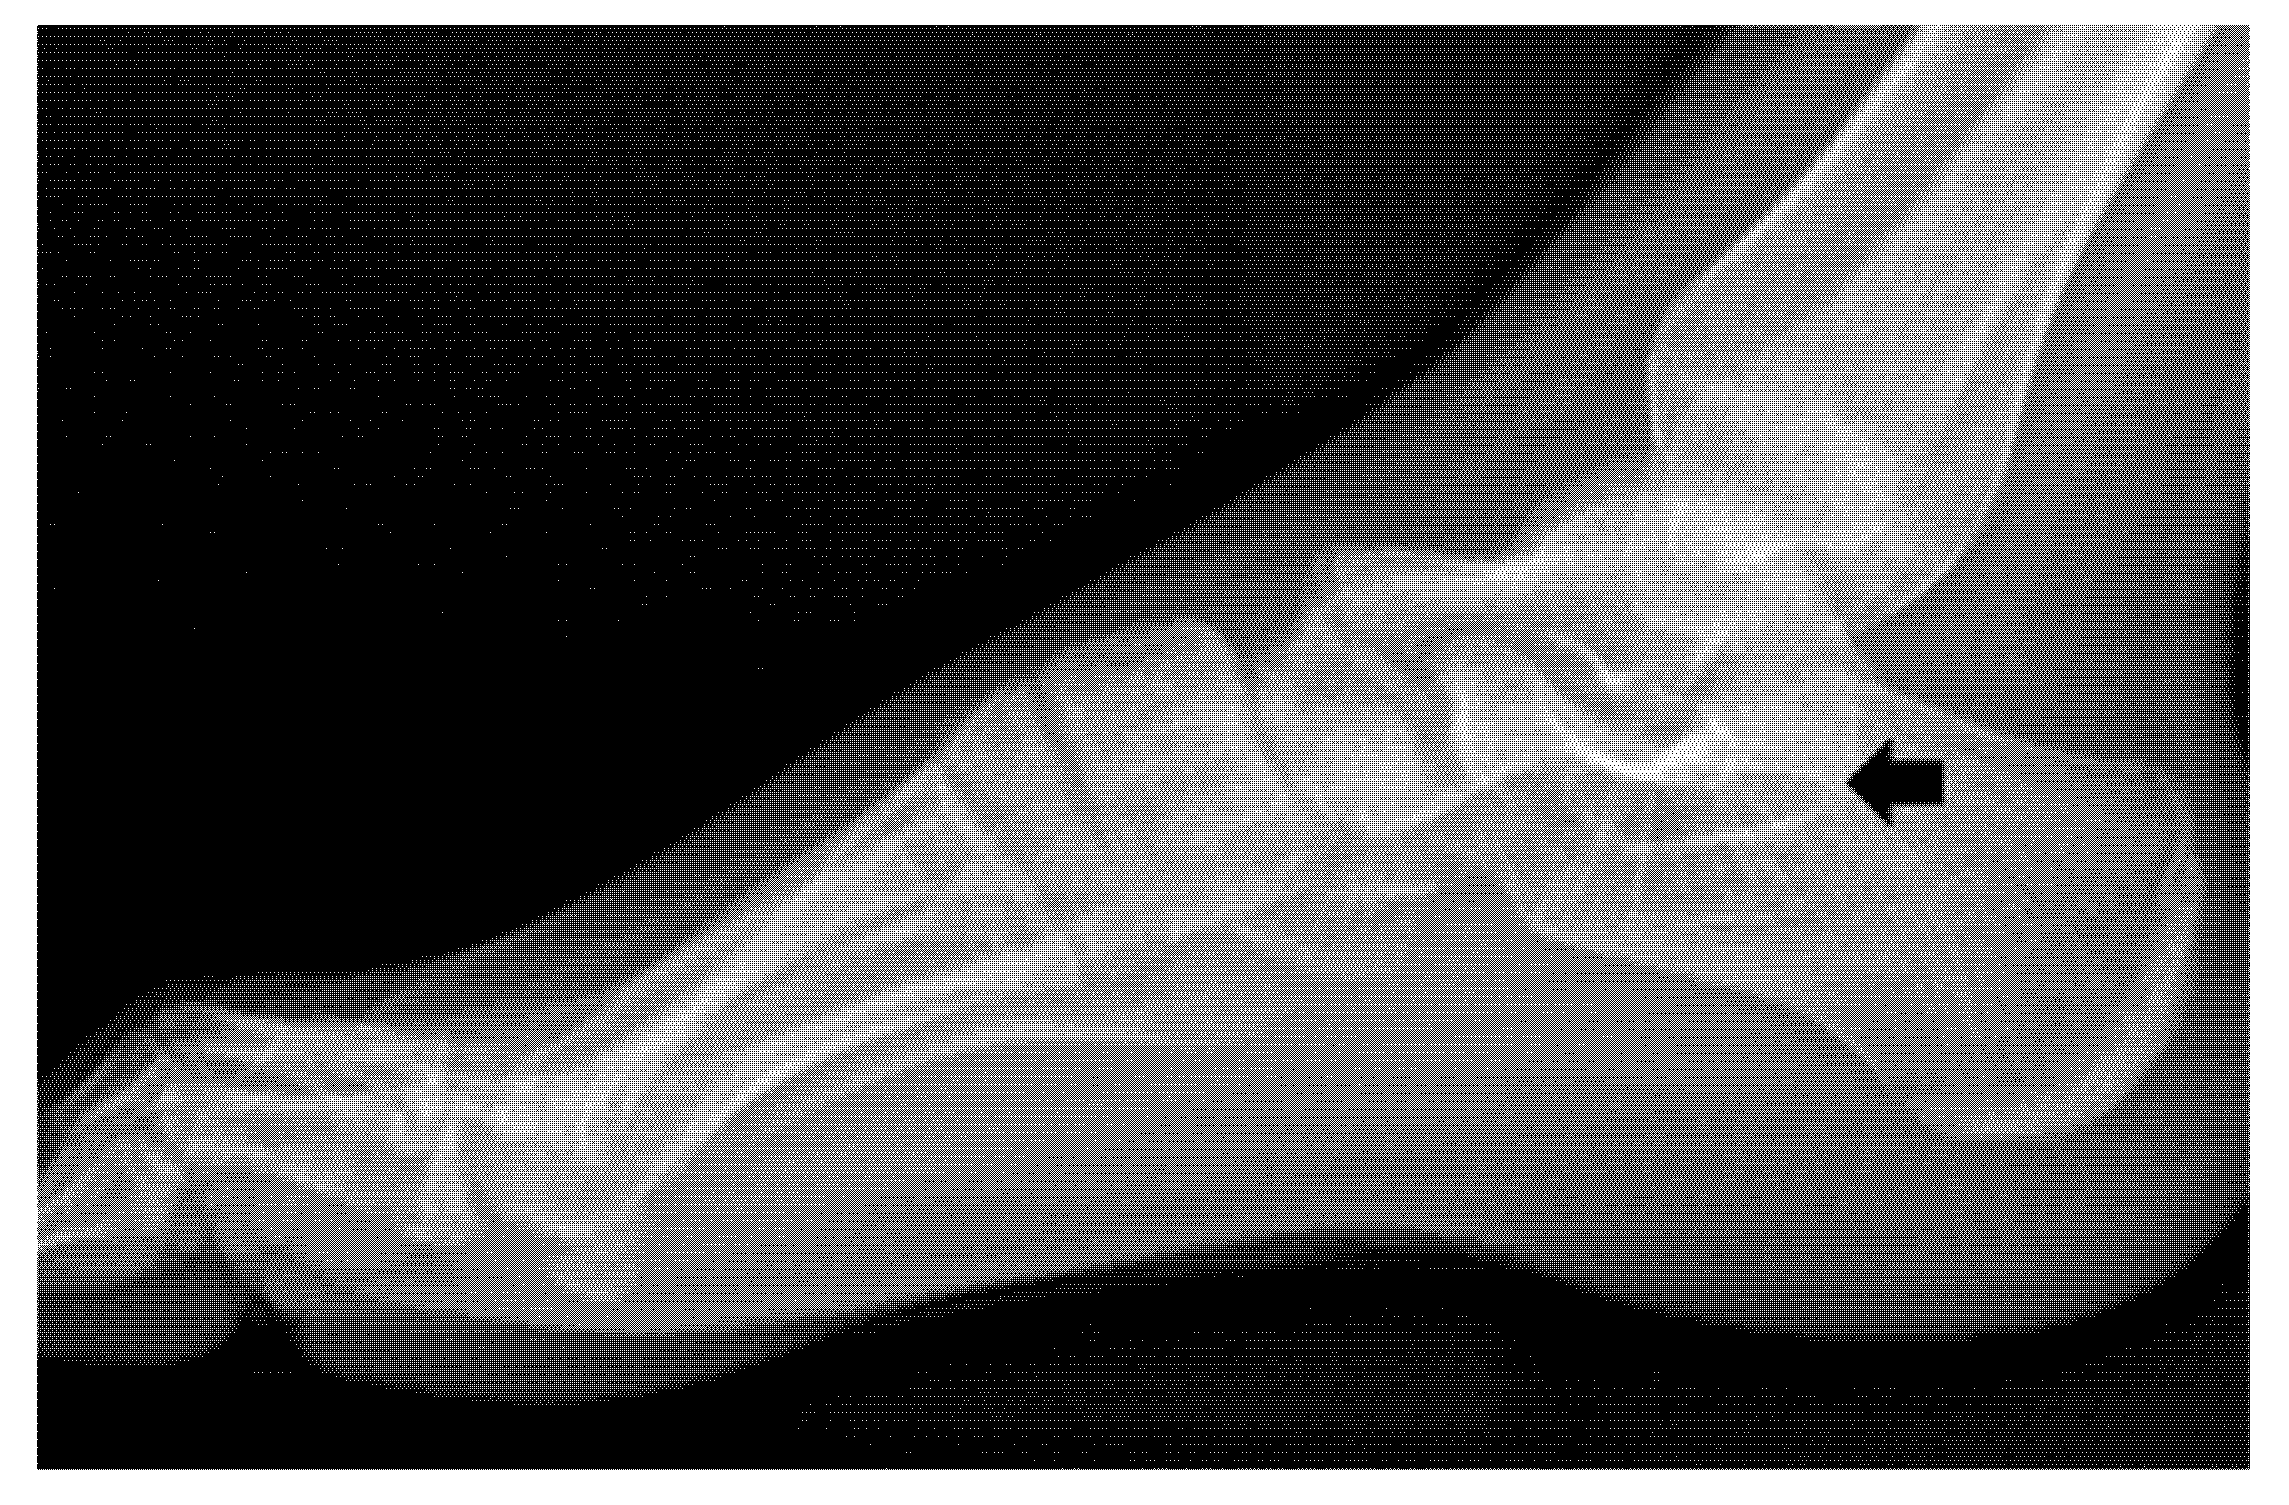

Bilateral Multiple Tarsal Coalitions (Talonavicular and Talocalcaneal Coalitions) with Recurrent Ankle Sprain in an Adolescent

2. Case Report